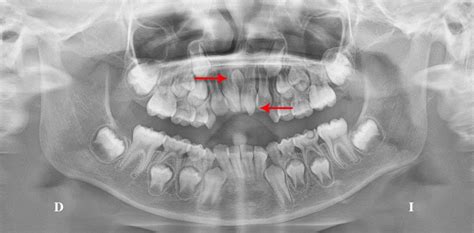

Radiografía mostrando la presencia de dientes supernumerarios impactados.

No es una anomalía frecuente, ya que el porcentaje de población que lo padece oscila entre el 2 y el 3%.Los dientes supernumerarios pueden aparecer de forma aislada o en grupos, y se desarrollan de manera similar a los dientes normales. En algunos casos, los dientes supernumerarios no son visibles a simple vista, ya que pueden permanecer impactados (es decir, debajo de la encía sin aparecer fuera) o desarrollarse en zonas difíciles de observar.

El diagnóstico de la hiperdoncia es fundamental para poder abordar correctamente esta condición y prevenir posibles complicaciones. La hiperdoncia suele ser asintomática, de forma que la detectará el odontólogo mediante las radiografías de seguimiento en consulta. Los especialistas en Odontología podemos distinguir los casos de hiperdoncia en una primera exploración, en función de la ubicación y la forma de los dientes numerarios.

El diagnóstico de la hiperdoncia generalmente comienza con una exploración clínica exhaustiva realizada por uno de nuestros dentistas. Durante este examen, se realiza un examen de la boca del paciente en busca de signos visibles de dientes adicionales. Por esto, se recurre a radiografías dentales para obtener una visión más detallada de la dentición del paciente. Las radiografías permiten observar no sólo los dientes visibles, sino también aquellos dientes que están por debajo de la superficie, como los dientes impactados o los que aún no han erupcionado.